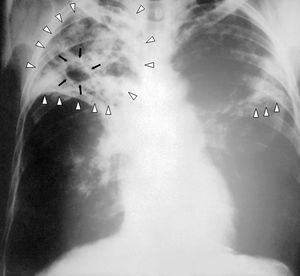

- Miliary TB

- Looks like millet seeds on CXR

- Immunocompromised patients less likely to have classic lesions and may have normal CXR